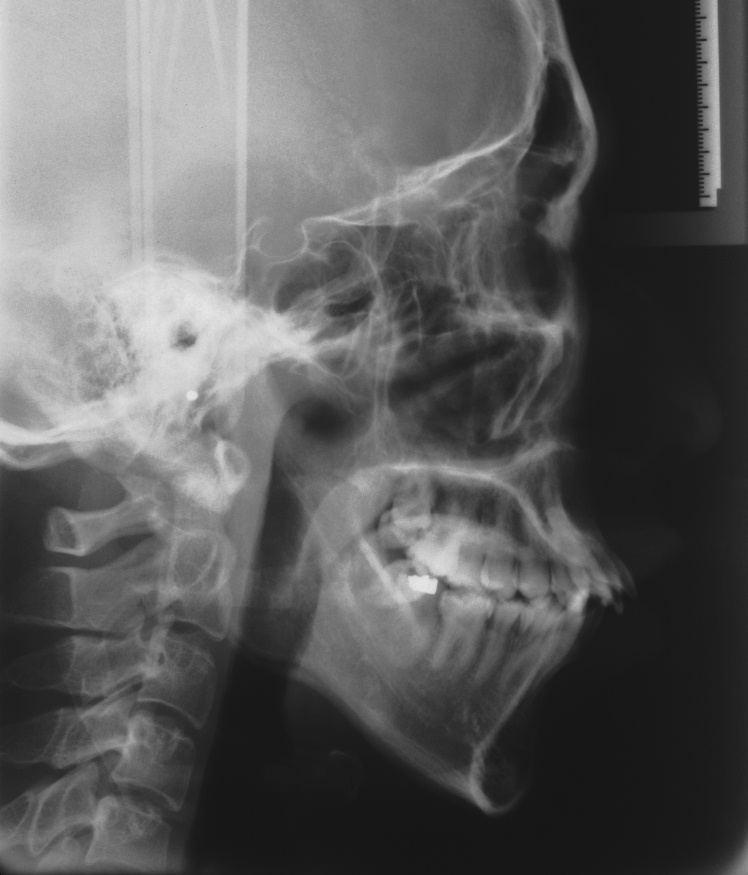

치료 후 사진입니다.